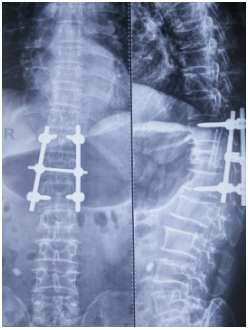

自7月上旬以來,我院骨科成功救治4例因外傷導(dǎo)致胸腰椎骨折患者。手術(shù)都很成功并取得了很好的治療效果,術(shù)后反應(yīng)良好,病人及家屬對此均表示非常滿意。骨科在王占厚主任的帶領(lǐng)下,針對每位患者的具體病情,積極控制原發(fā)病及并發(fā)癥,經(jīng)過數(shù)天的努力,在滿足手術(shù)指征的前提下,為患者成功進(jìn)行了手術(shù)。

目前,已有數(shù)名患者經(jīng)手術(shù)治愈,陸續(xù)康復(fù)出院,我院外科團(tuán)隊(duì)為此受到廣大患者及家屬的認(rèn)可。我院骨科雖成立較晚,但在醫(yī)學(xué)診療技術(shù)及護(hù)理團(tuán)隊(duì)綜合素質(zhì)都較成熟。骨科針對膝、髖、肩、踝等關(guān)節(jié)創(chuàng)傷和頸胸椎骨折等疾病的診治,開展有髖關(guān)節(jié)置換、全膝關(guān)節(jié)置換以及腰椎間盤突出髓核摘除術(shù)等各類骨科手術(shù),此外對胸椎結(jié)核病灶清除以及顱腦損傷,脊髓腫瘤等手術(shù)都有著很好的治療效果。

(上圖為患者術(shù)后X片)